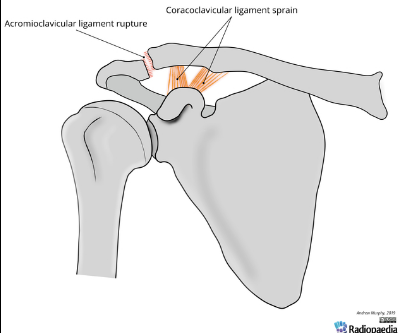

Based off Rockwood classification of acromioclavicular joint injury, what grade would this be?

2